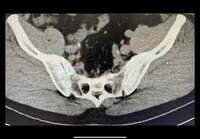

続けて「ありました、尿路結石!」と写真とともに述べ「もう何回目になるのだろう?」とコメント。「今回は約6ミリの石を確認」と明かし「一度痛みは来たのでもう来ないといいのですが」とつづり、ブログを締めくくった。